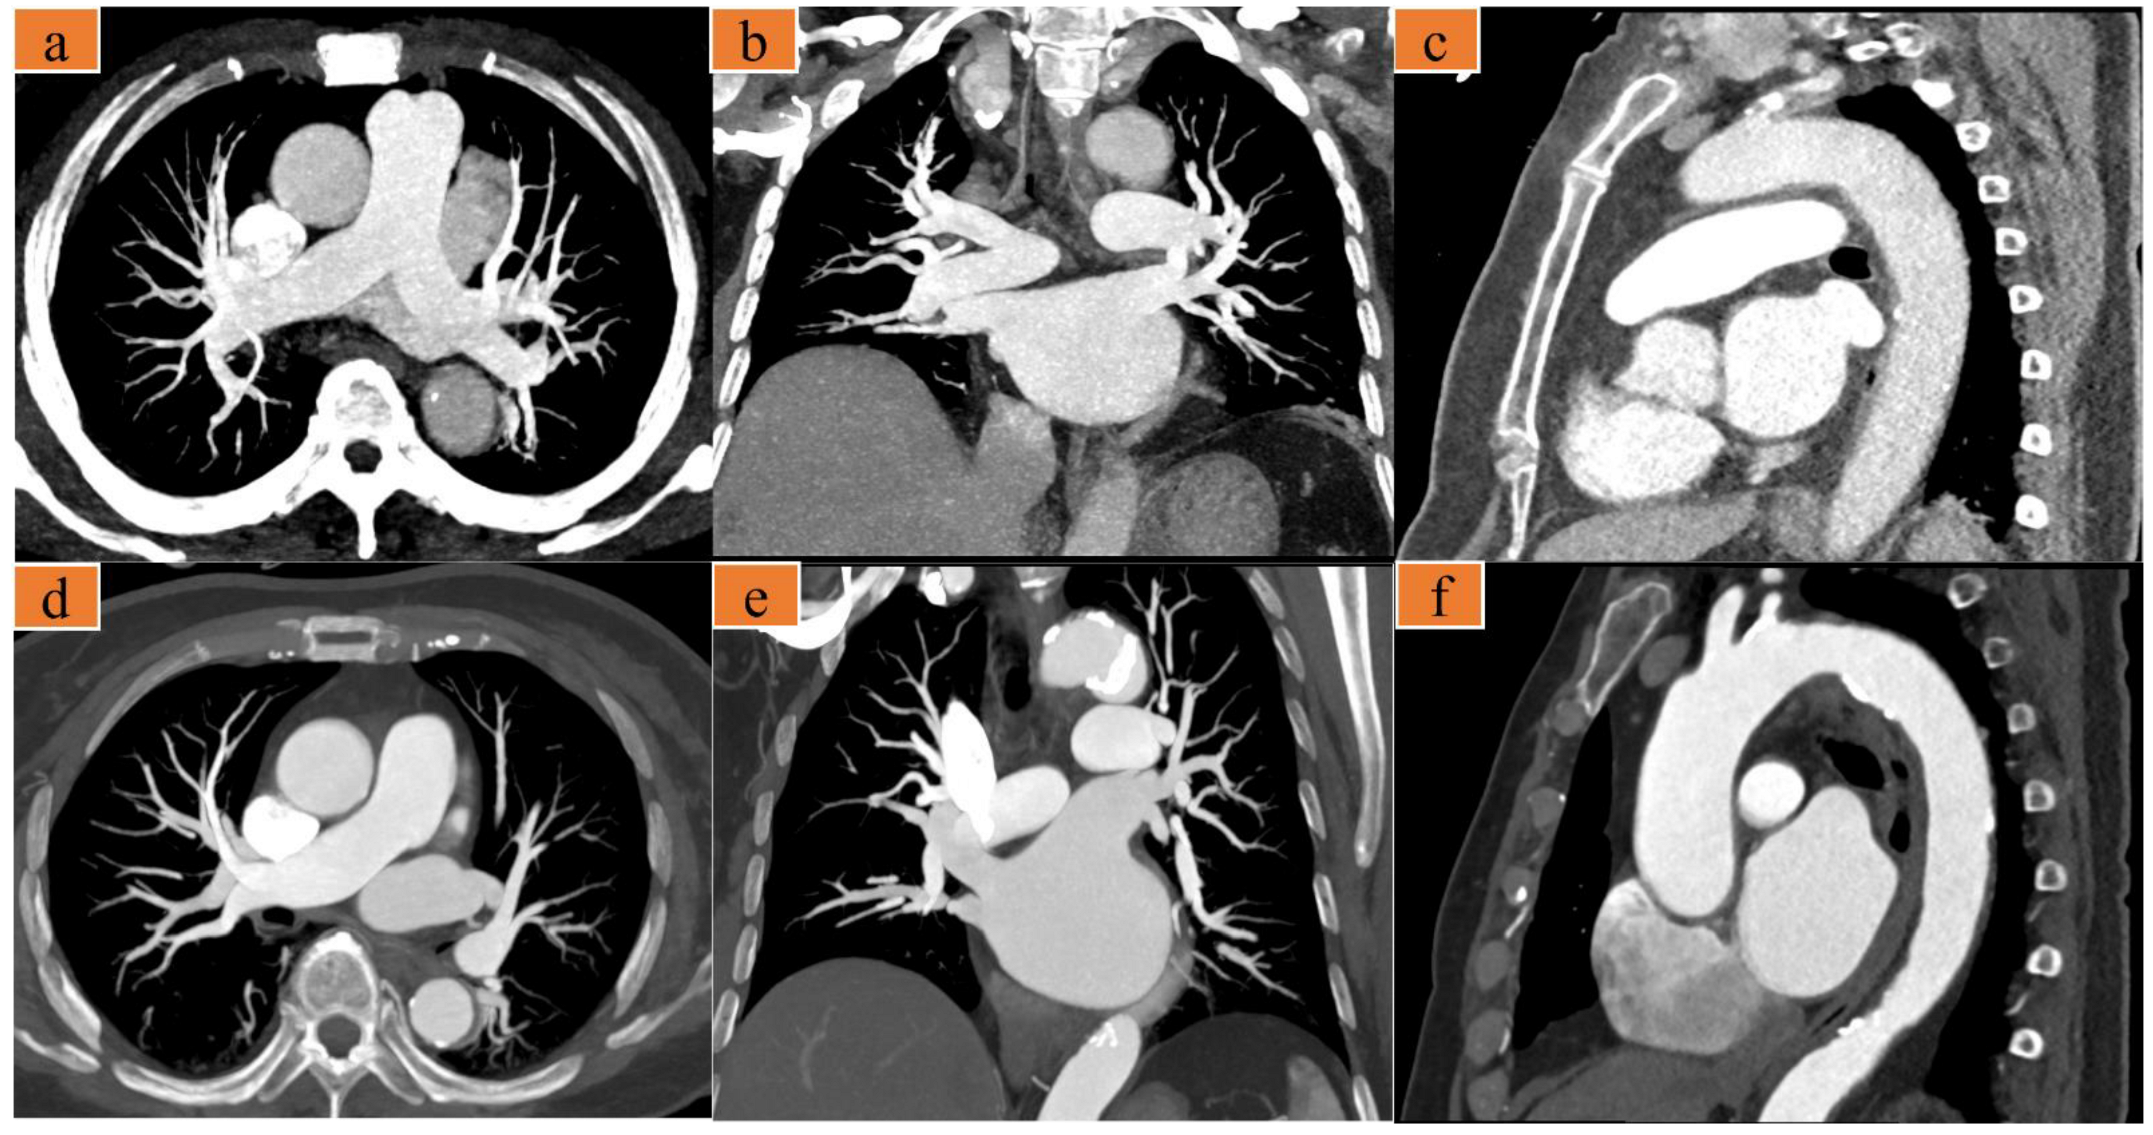

Dedicated CCTA Followed by High-Pitch Scanning versus TRO-CT for Contrast Media and Radiation Dose Reduction: A Retrospective Study

2.2. Image Acquisition